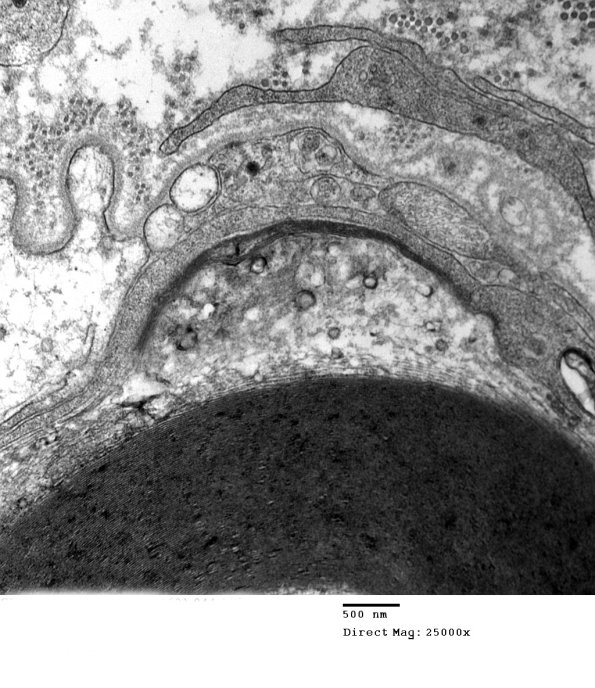

Only a thin process or two of an invading macrophage are visible resulting in a stripped myelin segment. (electron micrographs)